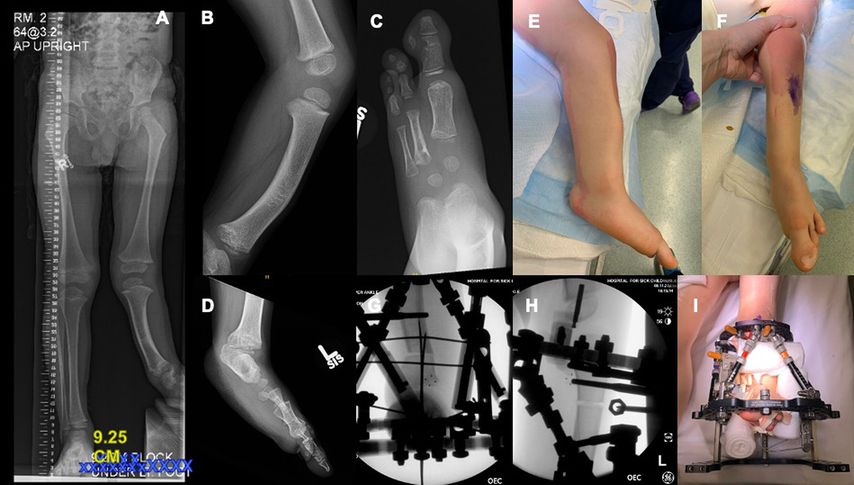

Abb. 2: 4 Jahre alter Junge mit Fibulahemimelie links (FATCO-Syndrom) mit Beinlängendifferenz von 8–9cm: Ganzbeinröntgen mit Ausgleich für Beinlängendifferenz (A), Valgus-Alignment mit fixierter Spitzfußstellung von 40°, „apex anteromedial tibial bow“ (B, E, F) mit „anteromedial skin dimple“. Der Rückfuß hat eine knöcherne Coalitio calcaneotalar (D), fehlender 2./3. Strahl, D1, D4, D5 vorhanden, D1-Syndaktylie (C, F). Die berechnete Beinlängendifferenz nach Abschluss des Wachstums betrug 12–14cm. Wir führten eine SUPER („systematic utilitarian procedure for extremity reconstruction“) Ankle Procedure durch, mit Dekompression des tibialen neurovaskulären Bündels, Resektion der Fibulaanlage, anteromedial Closing-Wedge-Osteotomie supramalleolar (G), „strayer gastrocnemius lengthening“, Anlage eines Taylor Spatial Frame Fixateur (I) zur Kallusdistraktion/Verlängerung und „midshaft tibia osteotomy“ (H)